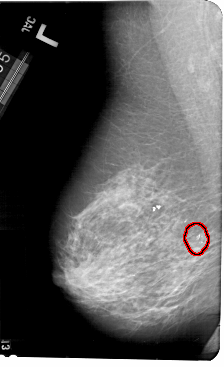

A_1496_1.RIGHT_CC

RIGHT_CC LINES 5386 PIXELS_PER_LINE 3196 BITS_PER_PIXEL 12 RESOLUTION 43.5 NON_OVERLAY

FILE: A_1496_1.LEFT_MLO.OVERLAY

TOTAL_ABNORMALITIES 1

ABNORMALITY 1

LESION_TYPE CALCIFICATION TYPE AMORPHOUS DISTRIBUTION CLUSTERED

ASSESSMENT 2

SUBTLETY 5

PATHOLOGY BENIGN

TOTAL_OUTLINES 1